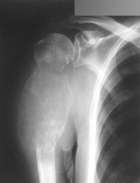

J.P. - 77 year old, right hand dominant, white male with a three month history of right shoulder pain and swelling

Zoom image: Radiological image Radiological image.